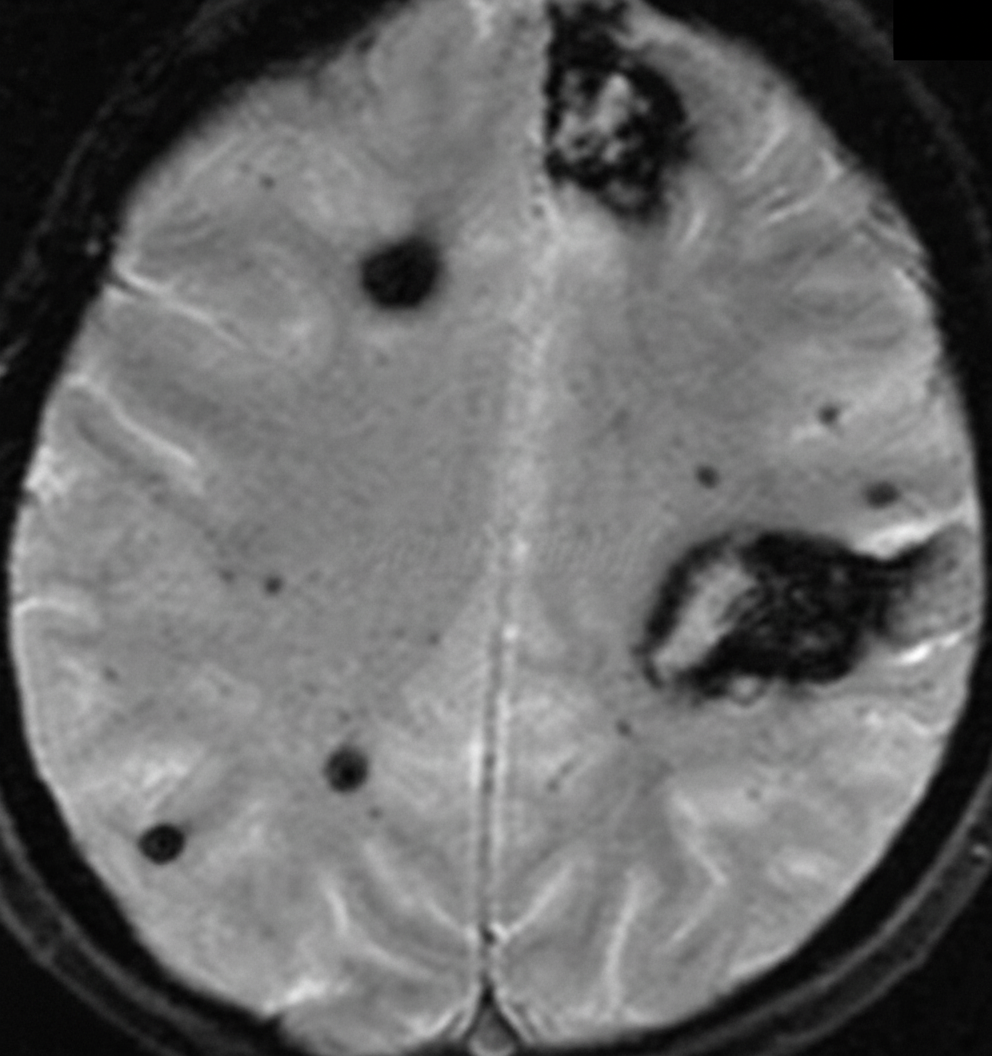

A 40-year-old man presented to the emergency room with loss of consciousness. He is a known alcoholic and hypertensive. His non-contrast CT head was normal, and his GCS is 8. An urgent MRI was performed. What is the most likely diagnosis?

Explanation: ***Diffuse axonal injury*** - **Normal CT** with severe neurological deficit (**GCS 8**) suggests microscopic injury requiring **MRI** for detection, characteristic of diffuse axonal injury. - **MRI sequences** like **SWI/GRE** show **microhemorrhages** at **grey-white junction** and **corpus callosum**, pathognomonic for DAI in trauma patients. *Cerebral amyloid angiopathy* - Typically affects **elderly patients over 65 years** with recurrent **lobar hemorrhages**, not a 40-year-old. - Characterized by **cortical-subcortical hemorrhages** in specific lobar distributions, not diffuse microscopic injury. *Subarachnoid hemorrhage* - Would be **visible on non-contrast CT** in acute phase (within 24-48 hours) as **hyperdense blood** in subarachnoid spaces. - Associated with **severe headache**, **neck stiffness**, and **photophobia**, not isolated loss of consciousness with normal CT. *Subdural hematoma* - Appears as **hyperdense crescent-shaped lesion** on **CT scan**, easily visible and would not require MRI for diagnosis. - More common in **elderly patients** or those with **brain atrophy**, presenting with **focal neurological deficits** rather than diffuse injury pattern.

Explanation: **Explanation:** The clinical presentation of an unconscious patient with a high-impact head injury, where CT findings show minimal mass effect (no midline shift) but significant signs of increased intracranial pressure (compressed basal cisterns) and punctate hemorrhages, is classic for **Diffuse Axonal Injury (DAI)**. **Why D is Correct:** DAI occurs due to sudden rotational acceleration/deceleration forces causing shearing of axons. The hallmark of DAI on imaging is **multiple small, petechial hemorrhages** located at specific interfaces: the grey-white matter junction (most common), corpus callosum, and brainstem. A key diagnostic clue is the **clinicoradiological dissociation**: the patient’s clinical state (comatose/GCS <8) is much worse than what the initial CT scan suggests. **Why Incorrect Options are Wrong:** * **A & B (Cortical Contusion/Laceration):** These are focal injuries typically found at the site of impact (coup) or opposite to it (contrecoup), usually involving the frontal and temporal poles. They present as larger, localized areas of edema and hemorrhage, often causing a midline shift. * **C (Multiple Infarcts):** These typically follow a vascular territory or "watershed" distribution and are usually seen in embolic events or severe hypoxia, not acutely following trauma with external injuries. **High-Yield Clinical Pearls for NEET-PG:** * **Gold Standard Investigation:** **MRI (specifically Susceptibility Weighted Imaging - SWI)** is the most sensitive sequence for detecting the microhemorrhages of DAI that CT might miss. * **Grading (Adams Classification):** * **Grade I:** Grey-white matter junction. * **Grade II:** Corpus callosum (Splenium). * **Grade III:** Brainstem (Dorsolateral aspect). * **Key Phrase:** Look for "Clinicoradiological dissociation" or "Normal CT in a comatose patient" to suspect DAI.